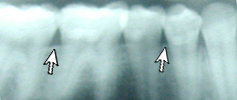

This patient has Periodontitis. Notice the

bone deterioration and uneven level of bone.